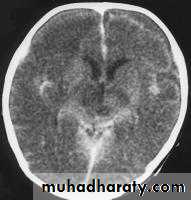

Bacterial Meningitis with cerebral oedema